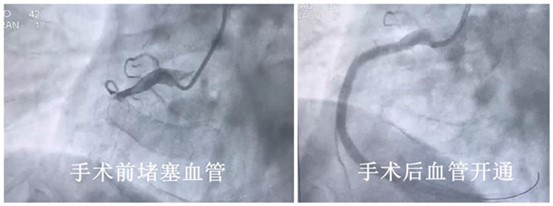

“患者右冠脈完全閉塞,迅速開通閉塞血管。”該院主刀的大內(nèi)科副主任何云發(fā)出了第一道指令。在專業(yè)的手術(shù)操作下,導(dǎo)絲通過閉塞病變血管、球囊擴(kuò)張,血流恢復(fù)。此時(shí)距離患者撥打120急救電話僅過去了67分鐘。

手術(shù)前后血管狀態(tài)。重慶康心醫(yī)院供圖